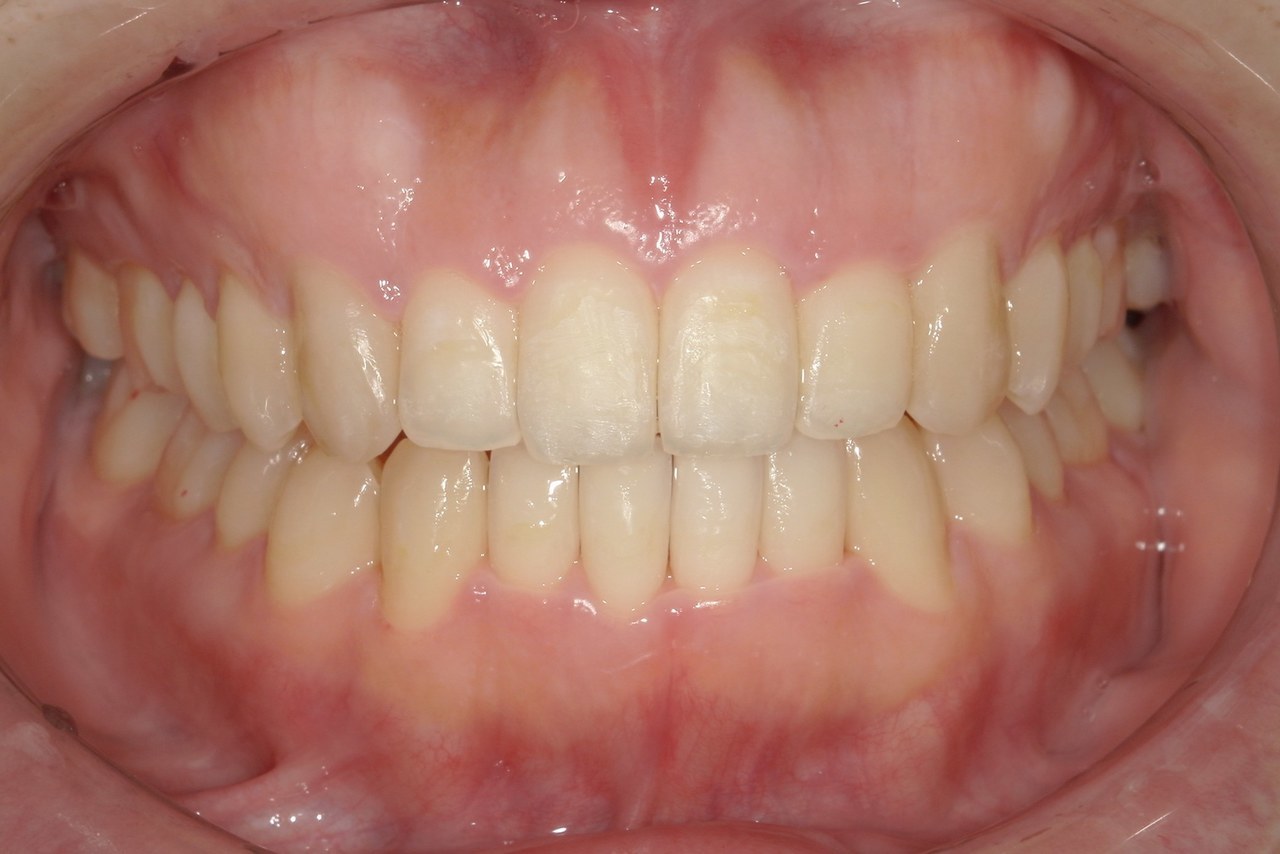

After

浜松市中央区・自動車学校前駅のインビザラインの症例

Y.S. 30代男性

全体的にガタガタしているのが気になるという主訴だったため、上下左右第一小臼歯を抜歯し、叢生を並べました。

治療の期間:R3. 9/1〜R5. 10/31

治療の価格:88万円